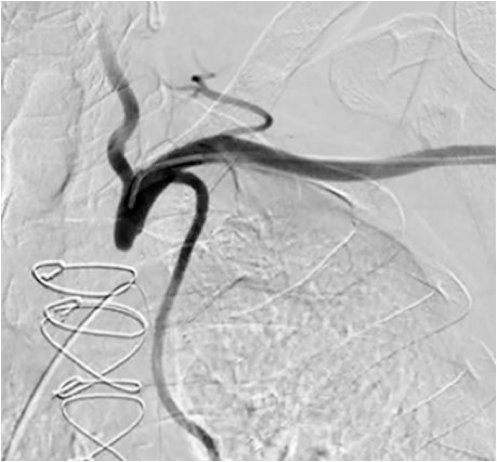

Figure 3. Right common carotid artery angiography: subclavian-carotid graft occlusion and surgical ligation of the right subclavian artery can be seen (click thumbnail to view larger image).

Upon transfer to our facility, a computed tomography angiogram (CTA) was performed, which revealed the bilaterally occluded bypass grafts and the ligated right SCA (Figure 2). Cardiac catheterization and angiography showed that both the proximal RCA and the left main were occluded. The SVG to RCA and OM1 were patent; SVG to D1 was occluded. The bilateral subclavian steals could be visualized with contrast injection into the bracheocephalic and left common carotid arteries (Figures 3 and 4). The LIMA was faintly visualized during the late filling phase of the left carotid angiogram (Figure 4); the left SCA and LIMA filled via collaterals from the left vertebral artery.